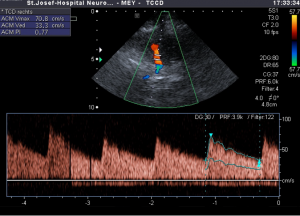

Το όνομα αυτής της μεθόδου προέρχεται από το συνδυασμό 1) της δισδιάστατης απεικόνισης του αυλού και της αιματικής ροής του αγγείου (duplex) με 2) την έγχρωμη απεικόνιση της κατεύθυνσης ροής του αίματος (colour). Έτσι προέκυψε η ονομασία της μεθόδου ως colour duplex ή triplex. (Εικόνα 2)

Εικόνα 2: Eξέταση triplex της αριστερής κοινής καρωτίδας αρτηρίας